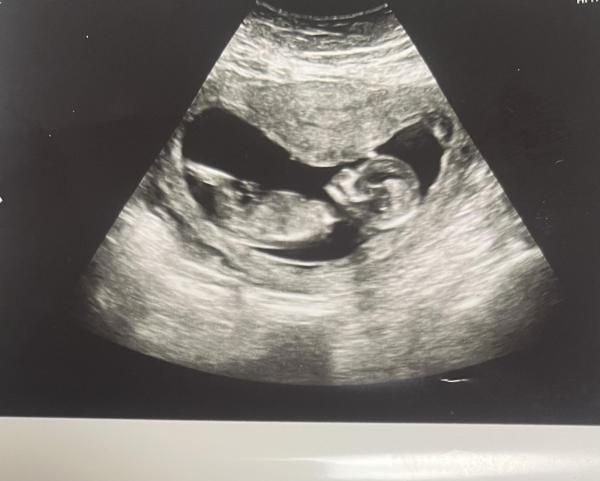

Hallo an alle Schwangeren und Mamis, wer kennt sich mit der sogenannten Nub Theorie aus? Ich habe schon einen Beitrag im Forum gepostet mit einem Bild vom "Geschlecht" leider ist dies aus der 11ten Woche und ich kann mir darunter nicht viel vorstellen. Heute hatte ich ein Termin zur NFM leider hat die Ärztin gesagt sie kann leider nichts erkennen und hat auch keine Tendenz. Ich habe zwei Bilder bekommen ich weiß leider nicht ob die gut sind. Ich gespannt auf eure Antworten ind vil kann mir jemand die Nub Theorie einmal genau erklären 😅

Bild zu Wer hat Ahnung von der Nub Theorie - Schwanger - wer noch? Rund um die Schwangerschaft